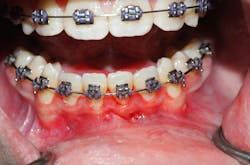

Clinically, there was no buccal or lingual expansion (figure 1). The patient’s medical history was noncontributory. A CT scan revealed a 1.5 cm x 1 cm well-defined, circular, hypodense area inferior to the lower incisors (figures 2–4).